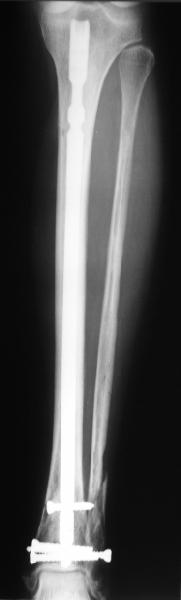

A typical case is attached, also an image with intra-op reduction obtained by a small wire distractor, in the moment of insertion a Poller wire in AP direction. Fixation by a SIGN nail. Despite the fibula was not fixed healing was obtained with the unchanged alignment.

[ Ответить ]